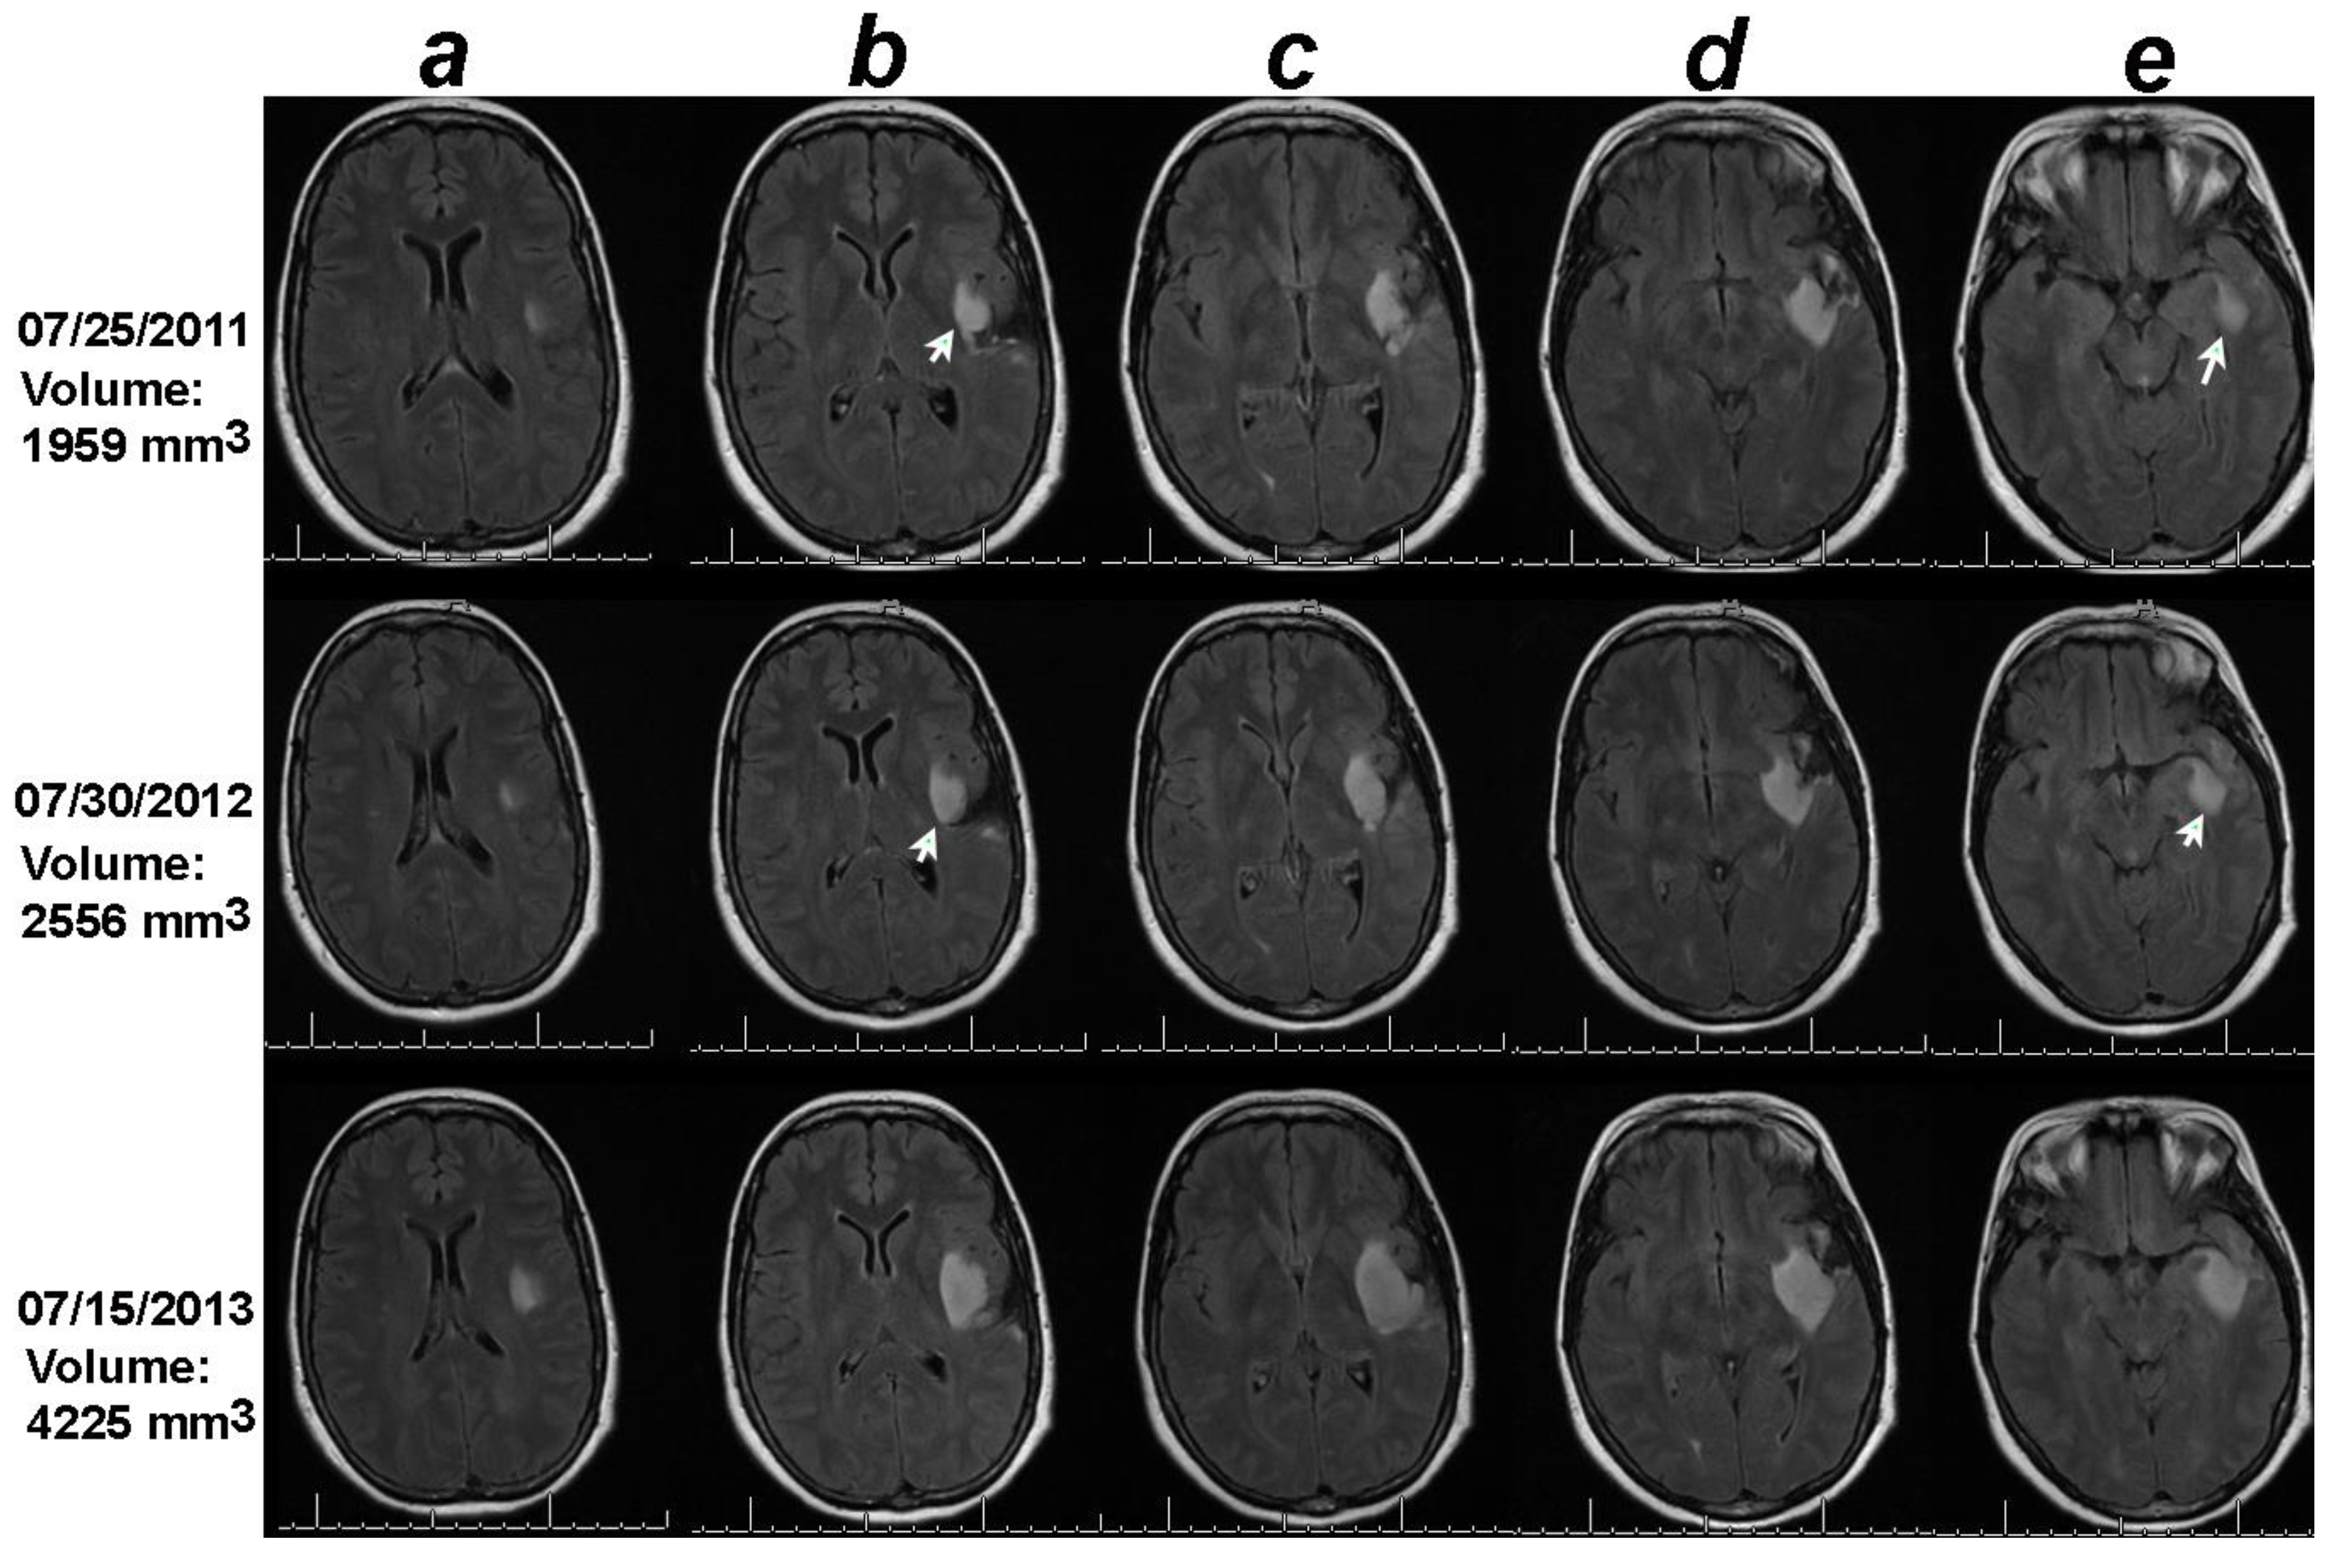

Figure 1. Volumetric analysis combined with the online change-of-point statistical method detects progression on 07/30/2012, one year earlier than the date of progression documented in the clinical notes (07/15/2013). Notice that though the tumor in the 2D sections containing the largest tumors under columns c and d did not change between the baseline (07/25/2011) and 07/30/2012, the 2D sections in columns b and e increased in size between the baseline MRI of 07/25/2011 and date of progression detected by the change-of-point method, 07/30/3012 (white arrows). .